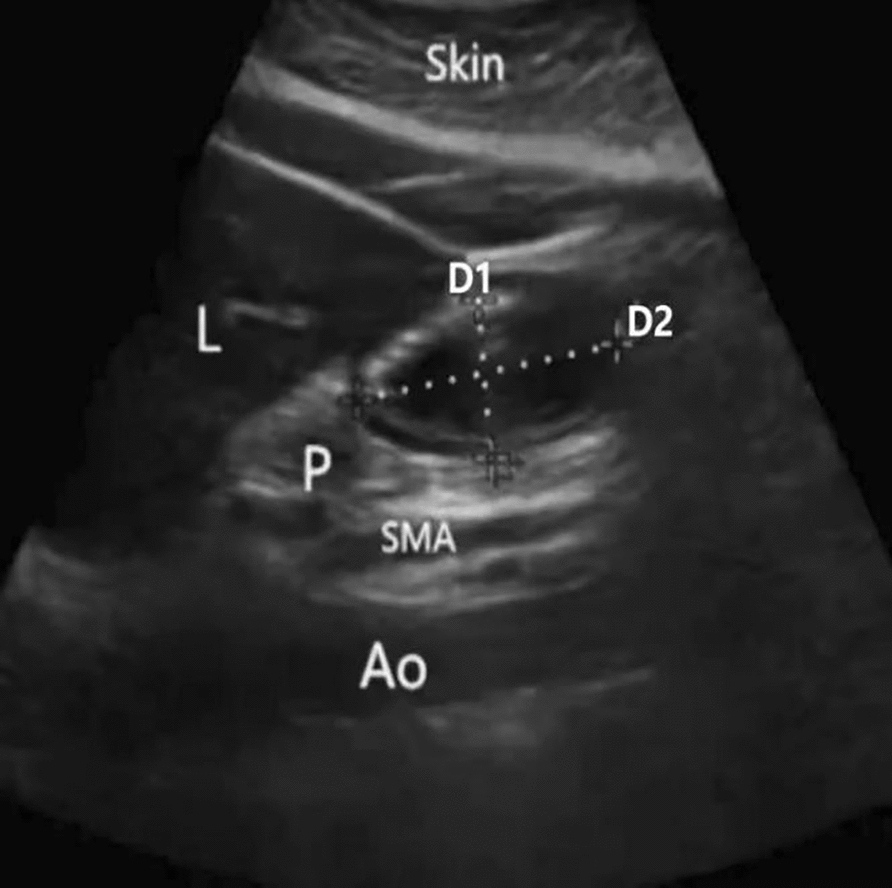

Methods: Fifty-eight patients scheduled for elective NTSR were randomly assigned to Group A (n = 29), who received 400 mL of 10% glucose solution orally 2 h before anesthesia, or Group B (n = 29), who fasted for at least 8 h. Gastric ultrasound was used to measure antral diameters before induction and after surgery, from which GV was estimated. BG levels were recorded at fasting (T1), before induction (T2), and after surgery (T3). The incidence of PONV within 24 h, reflux aspiration, and hospital stay duration were also assessed.